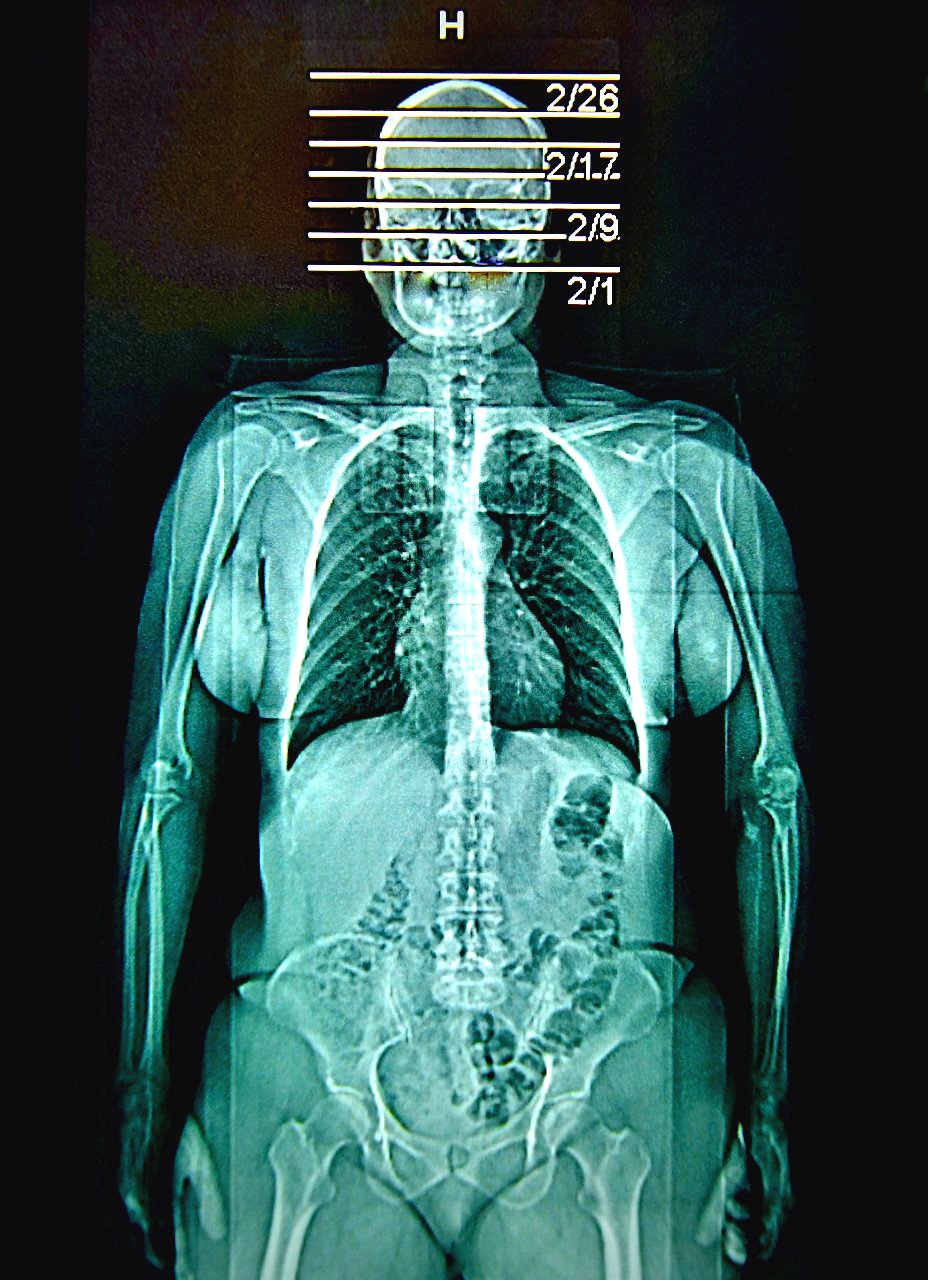

saturday night fever (boy meets girl diptych)

Selected for July/Aug 2022 exhibition in Art No.23’s Barcelona gallery.